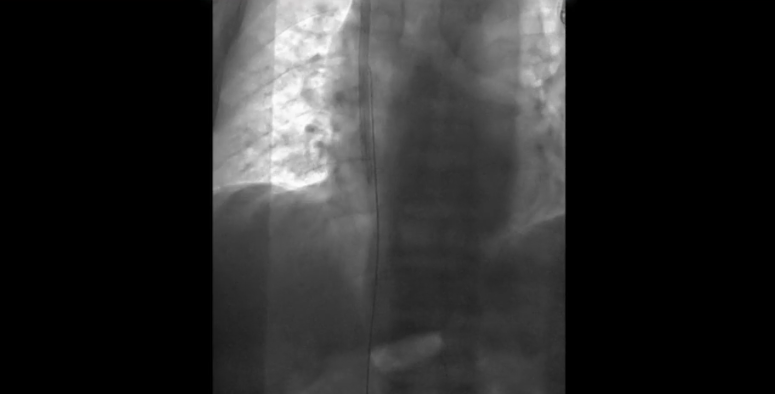

Segmento de guía metálica retirado mediante catéter lazo.